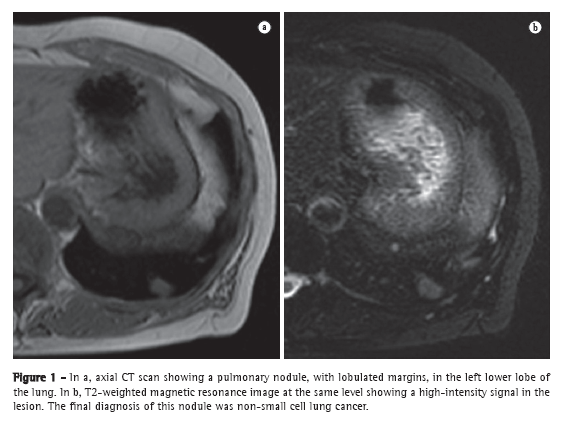

ECG

In patients with PH, ECG can show increased P wave amplitude (≥ 2.5 mm in the DII derivation), signs of right ventricular hypertrophy, right bundle branch block, right QRS axis deviation, and repolarization changes (right ventricular strain). Although a deviation greater than 100° has been shown to correlate well with hemodynamic measurements, its specificity for the diagnosis of PH has been shown to be low. Up to 13% of the patients with a diagnosis of PH confirmed by right heart catheterization (RHC) can initially present with normal ECG results (Figure 1).(3)